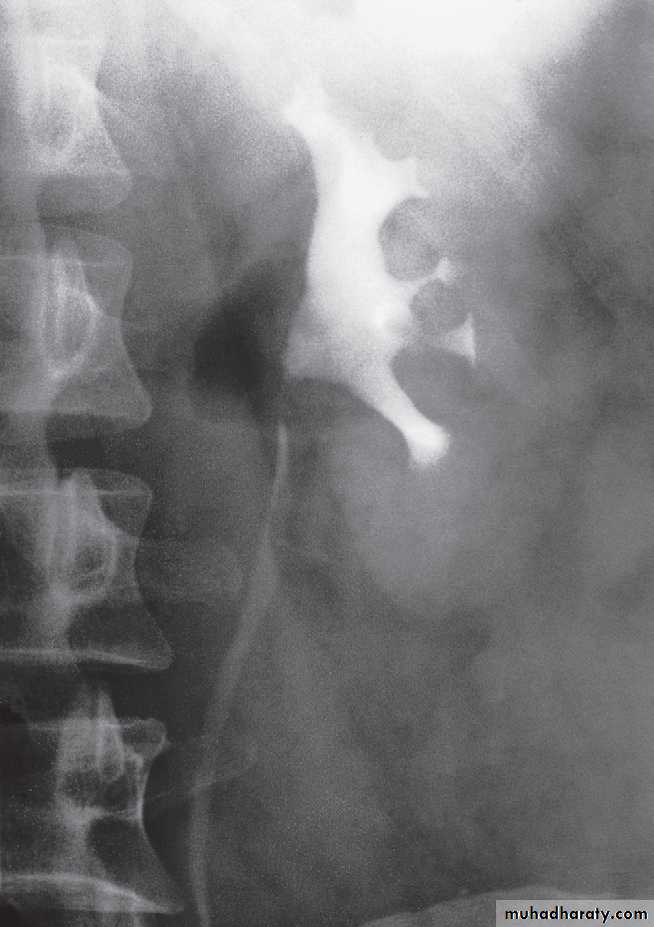

Retrograde and antegrade pyelographyThe techniques of retrograde and antegrade pyelography (the term pyelography means demonstrating the pelvicaliceal system and ureters) involve direct injection of contrast material into the pelvicaliceal system or ureters through catheters placed via cystoscopy (retrograde pyelography) or percutaneously into the kidney via the loin (antegrade pyelography).

The indications are limited to those situationswhere the information cannot be achieved by less invasive means, e.g. IVU, CT or MRI to confirm a possible transitional cell carcinoma in the renal pelvis or ureter.